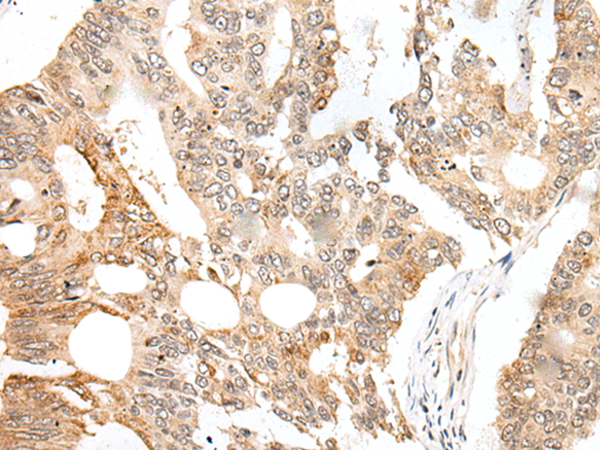

IHC positive control: |

Human colorectal cancer |

IHC Recommend dilution: |

25-100 |